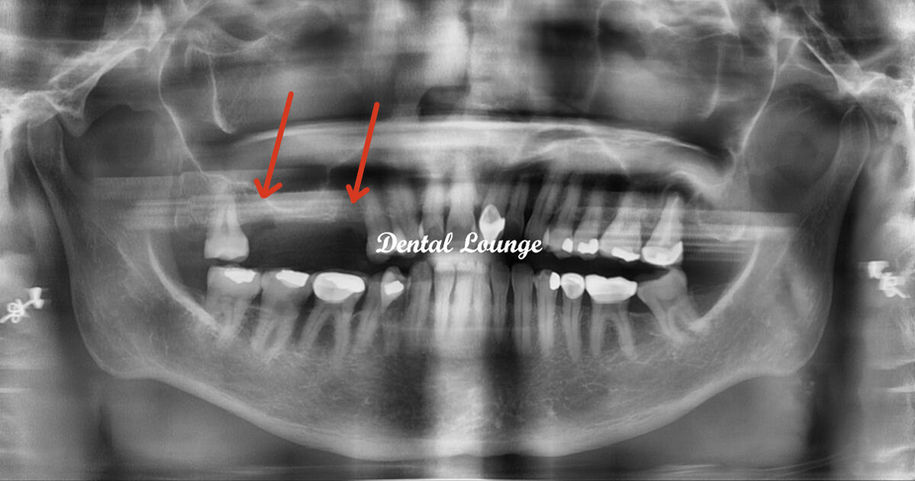

Retained root removal is a routine surgical procedure used to extract fragments of tooth roots left behind after a fracture or incomplete extraction. The process begins with diagnostic imaging to locate the root and assess its depth. Under local anaesthesia, your dentist will access the area, remove any bone if necessary, and extract the root using precise instruments. The site is then cleaned, sutured, and allowed to heal. This straightforward treatment helps prevent infection, restores oral health, and prepares the area for future procedures such as dental implants. With modern techniques, most patients find the experience comfortable and recovery uncomplicated.

How do you know if I have retained roots?

X-rays or 3D imaging reveal fragments that may not be visible or causing symptoms yet.